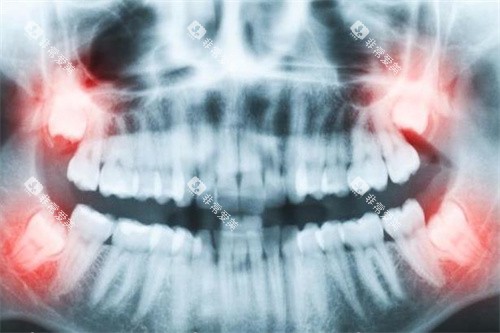

作为浙江东部口腔连锁龙头,牙贝恩在灵溪镇的旗舰店堪称“技术流头牌”。2000㎡的诊疗空间里,5大核心科室(种植、正畸、修复、牙周、儿童口腔)分工明确,数智化口腔全景机、瑞士种植机等设备一应俱全。其种植团队由集团种植院长尉子龙领衔,这位在牙槽骨缺失修复领域造诣深厚的医生,能熟练开展上颌窦脊顶提升种植、前牙美学种植等高难度手术,甚至能实现“快速种植即用”的all-on-4全口种植技术。

在正畸领域,牙贝恩的“美学矫治”理念深受年轻人追捧。金属托槽、隐形矫正、儿童早期干预等八大系统覆盖全年龄段需求,更引入智能化口扫仪,3分钟即可生成3D矫正方案,让患者提前看到矫正后的结果。2025年8月,该机构因“智能化种植牙技术”入选温州牙齿搭桥术口腔医院综合实力前十强,技术实力获官网认证。